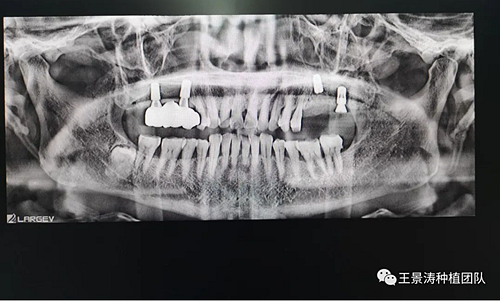

左側(cè)下頜第二磨牙及右側(cè)下頜第一磨牙同時即刻種植病例。患者年輕女性,無系統(tǒng)性疾病。37及46殘冠及殘根,且46劈裂,無法冠修復(fù),必須拔除。37根尖慢性炎癥,大量肉芽組織存在,46根分叉較高,根分叉骨質(zhì)尚可。CBCT示:根尖骨質(zhì)至下牙槽神經(jīng)管距離可滿足種植體的初期穩(wěn)定性,遂考慮即刻種植,并在種植體周邊填入骨粉并覆蓋骨膜,雙側(cè)的種植體初期穩(wěn)定性相差無幾,但考慮到37根尖慢性炎癥較大,遂給予埋入式種植。